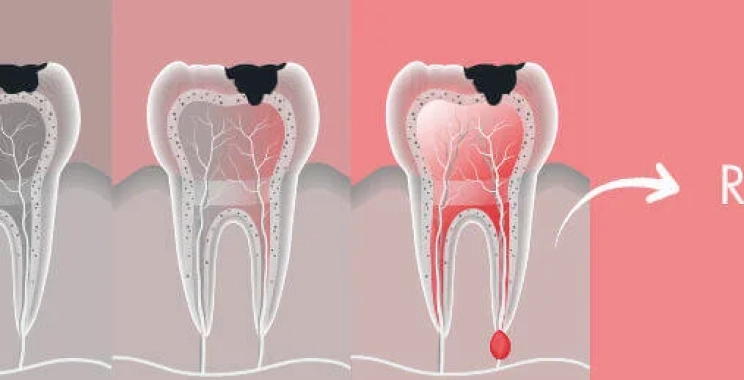

الفرق بين ألم التسوس وألم العصب

تسوس الأسنان من الأعراض الشائعة التي تصاب بها الأسنان نتيجة تراكم بقايا الطعام وعدم الاهتمام بنظافة الأسنان بصورة مستمرة.

ولكن ألم التسوس يختلف عن ألم التهاب عصب الأسنان. حيث أنه يحدث نتيجة تسوس عميق في الأسنان لا يمكن علاجه ويسبب انتفاخ اللثة حول الضرس أو السن.

ويأتي الفرق بين ألم التسوس والعصب في شدة الألم الذي يشعر به المريض ومدته. حيث يكون ألم التسوس بين الخفيف والمتوسط ويزداد عند تناول الطعام السكري أو المشروبات الباردة ويختفي مع توقف تناول هذه الأطعمة.

في حين أن ألم العصب يكون شديدًا ويستمر لفترات طويلة قد يكون في صورة نبضات تصل إلى منطقة الأذن ولا يختفي بالمسكنات.